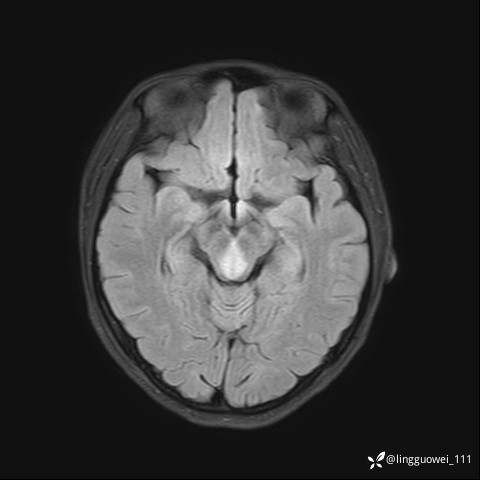

img

T2压水